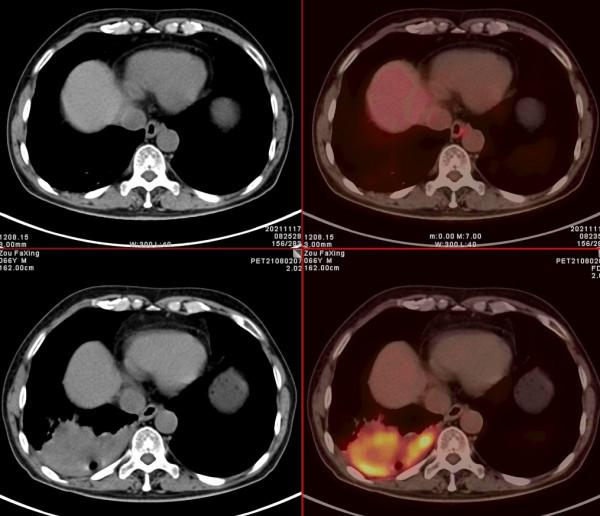

依據影像學分期,該患者後續進行了綜合治療:免疫+化療+靶向治療,其中化療3期,免疫治療2期及靶向治療。3個月後患者再次進行了PET/CT檢查,對治療效果進行了評估。2021年11月PET/CT檢查結果:

腫瘤病灶明顯縮小、實性成分明顯減少,腫瘤FDG代謝明顯減低,相鄰胸膜浸潤明顯改善,已經沒有胸水徵象。另外,全身其他部位未見明確轉移性病變。

複查後PET/CT診斷:右肺下肺癌綜合治療後,腫瘤病灶明顯縮小,FDG代謝明顯減低,相鄰胸膜未見高代謝病變,考慮腫瘤治療後療效顯著,僅少量腫瘤活性殘留。